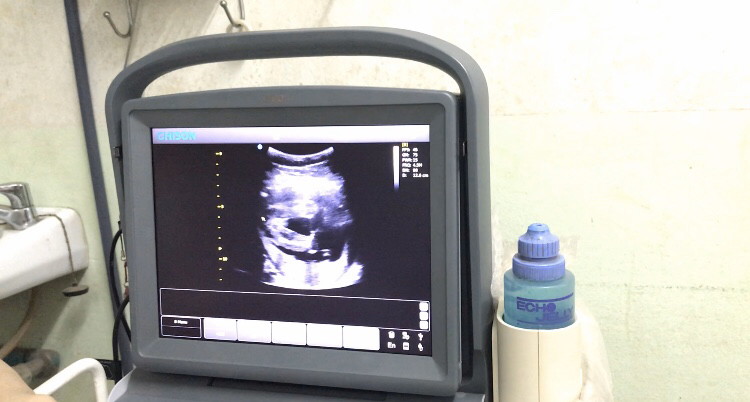

ตั้งครรภ์20week

ซาวด์ตอน19+3 ค่ะ